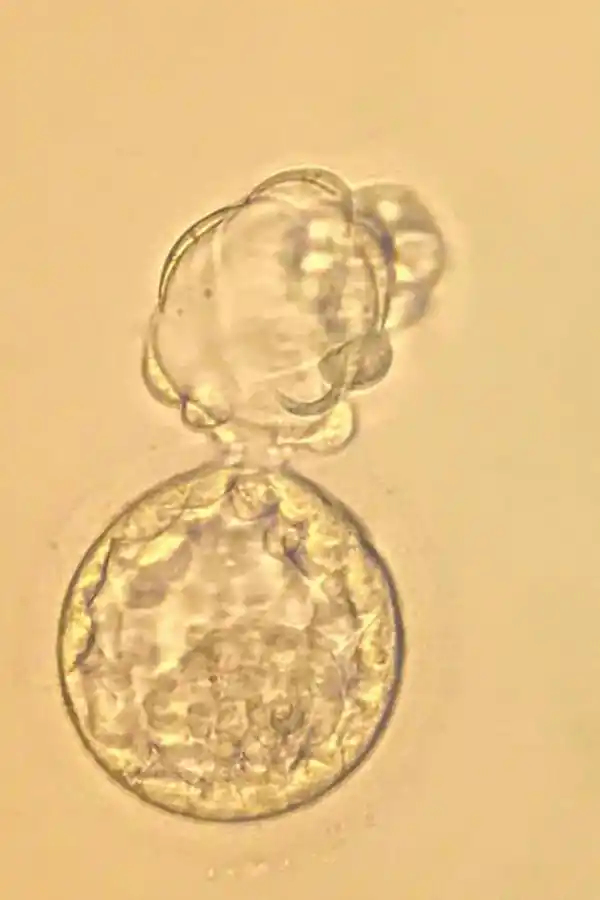

1 Ovocito inicial recién donado.

3. Embrión en el quinto día.

3. Embrión a 6 eclosionando

2. Embrión en el tercer día de vida.